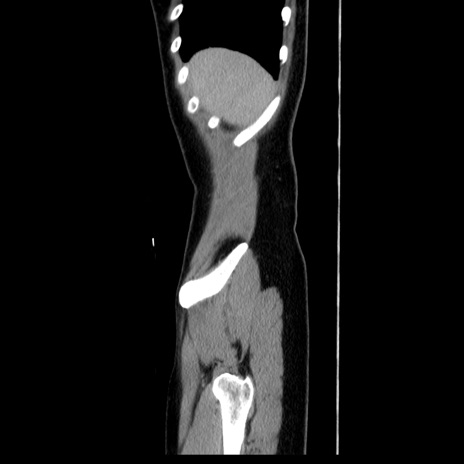

症例39(矢状断像)

【症例】40歳代女性

【主訴】上下腹部痛

【現病歴】2日目から下腹部痛あり。夜間は痛みで眠れなかった。昨日より上腹部痛と下痢が出現。臥位で痛みは軽快したため、休んでいた。本日になって臥位でも立位でも痛みが強くなってきたため救急要請。

【既往歴】子宮内膜症

【身体所見】部:平坦・軟、左上下腹部に圧痛あり、反跳痛あり。

【データ】WBC 21800、CRP 26.78

CT